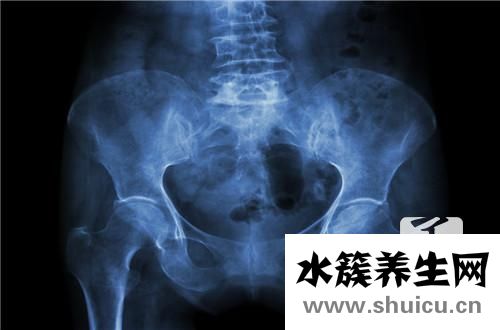

盆腔積液是一種常見的身心健康問題。如果盆腔積液超過10Mm,則屬于生理盆腔積液。這種盆腔積液對女性的身心健康是有害的,也會在疾病發(fā)生時給女性造成各種痛苦。比如肚子很疼,很可能是生理性的盆腔積液。下面我們來介紹一下盆腔積液!

盆腔積液便是骨盆存有炎癥性滲出液,可產(chǎn)生在子宮壁炎癥后,子宮內(nèi)膜組織發(fā)脹的體細(xì)胞中外滲的略粘稠的液體,被周邊組織包囊所逐漸產(chǎn)生的囊性包塊。如果不多方面醫(yī)治得話,能夠慢慢長大。中藥材外治法可使藥力直通疾病,足以迅速充分發(fā)揮功效,快速改進(jìn)傷處生理作用,修補(bǔ)發(fā)炎組織。御雪清治療盆腔炎、盆腔積液以其安全性無副作用,故醫(yī)治盆腔炎癥中醫(yī)學(xué)是最好的選擇。除開女士因生理特征有一切正常的盆腔積液外,生理性的盆腔積液多是盆腔炎或孑宮內(nèi)膜異位癥。盆腔積液可產(chǎn)生在盆腔炎、附件炎或孑宮內(nèi)膜異位癥以后。按病理學(xué)要素可分成生理性盆腔積液和生理性盆腔積液二種。生理性盆腔積液對女士而言并不是是一件壞事兒,生理性盆腔積液傷害很大,一旦女士出現(xiàn)異常盆腔積液,應(yīng)立即到醫(yī)院門診就醫(yī),用藥治療。